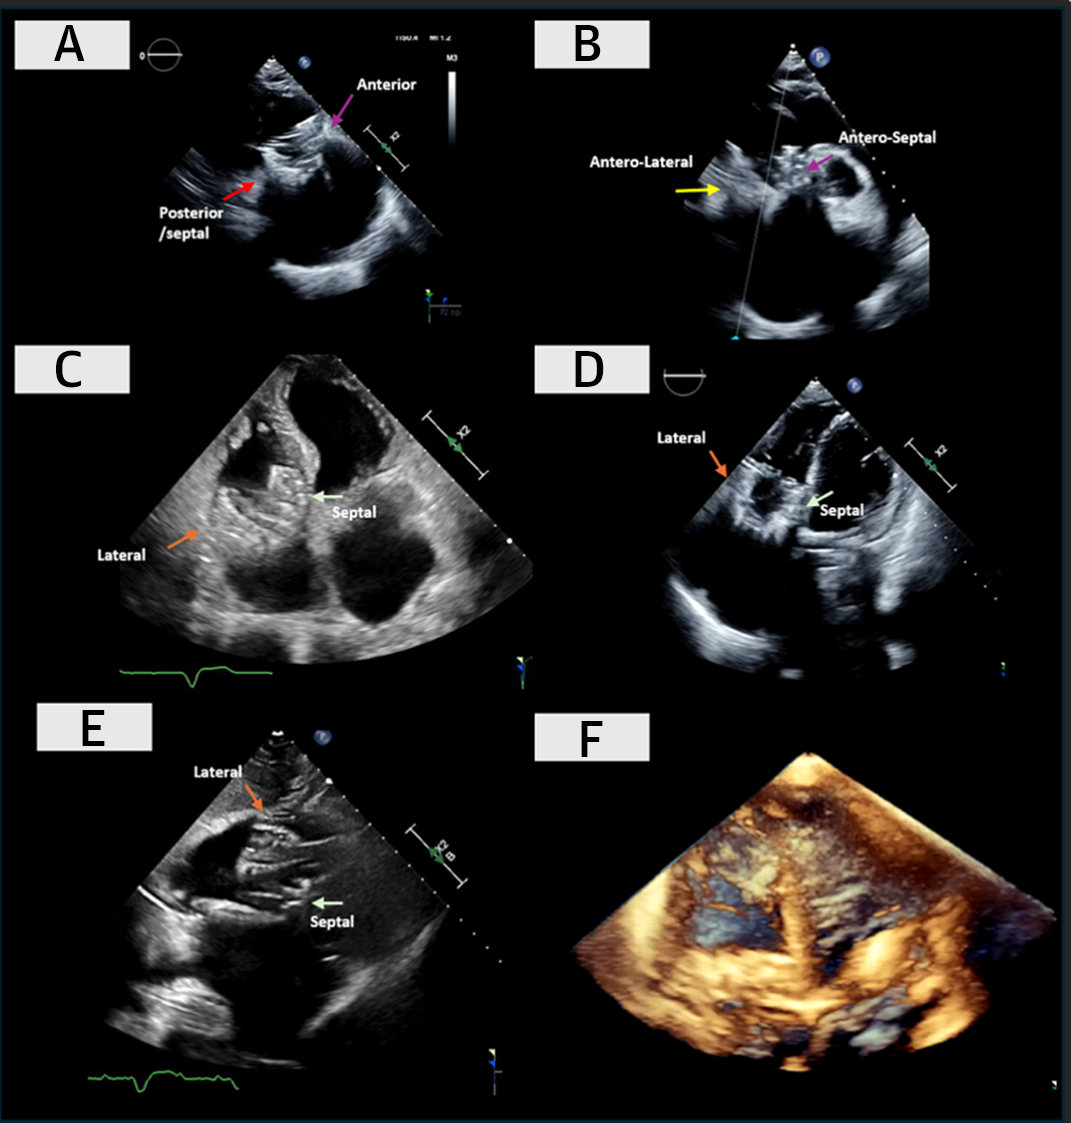

JUST OUT on actual ANATOMIC visualization of the 5-type morphological classification of #TricuspidValve anatomy published previously by @hahn_rt et al, now correlated with #Echo #TEE and schematic by @juliendreyfus1 et al. in #JACCIMG @JACCJournals . A MUST-READ and print-out